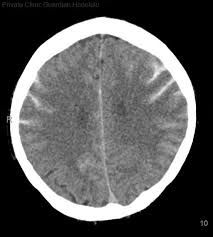

anoxic brain injury post-arrest

loss of gray-white differentiation

swollen sulci, small ventricles

pseudo-SAH from proteinacous leakage into subarach space